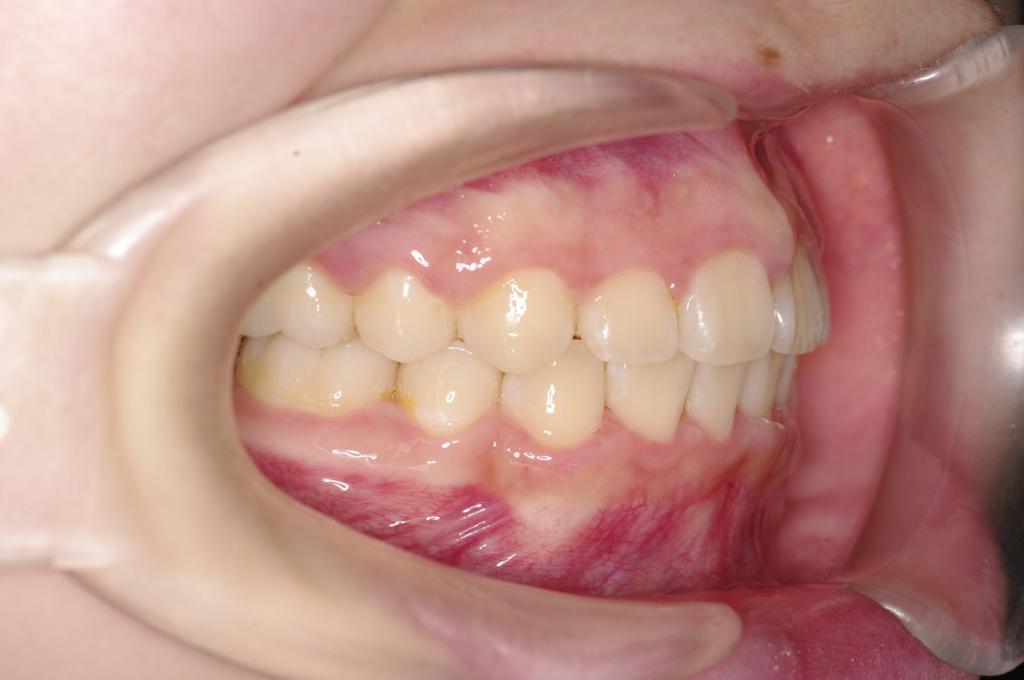

前歯、出っ歯・開咬の矯正治療

(治療期間、治療前後写真、治療方法、費用)WORKS